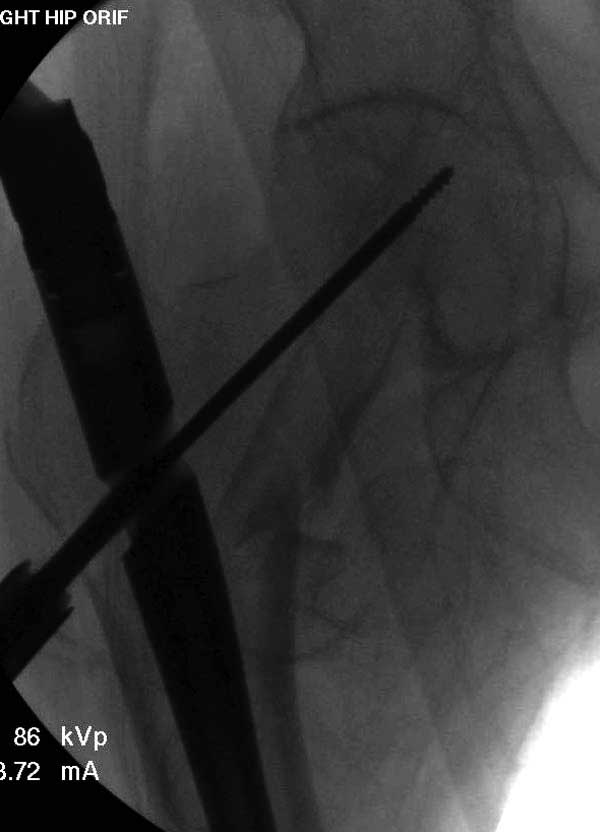

Первые снимки показывают технические погрешности установки DHS. Не была достигнута репозиция, конечность в флексии и шейка в ротации. Сегодня все меньше обращают внимание на параметры для оценки репозиции (S контуры Lowell в обеих проекциях и Garden Alignment Index, в норме 155 и 180 градусов), хотя такие простые тесты помогли бы дорепонировать смещение. Винт находится сзади в головке, что при нагрузке поменяет вектор и вместо компрессии в линии перелома срежет головку-Cut Out!

Такие “чужие осложнения” встречаются у всех и представляю банальный случай, который шаг за шагом показано как перерос в более сложный процесс... Больная 70 лет, множественные ко-морбидности, чрезвертельный перелом первоначально фиксирован Гамма 3. Осложнение в течение 6 недель, ревизия тотальной артропластикой и во время установки ножки обнаружена трещина диафиза (17), из малого доступа фиксация алло-графтом.

Повторно поступает после двух с половиной лет, где обнаруживается перелом на второй стороне. Немного сложно, но для фиксации выбрали Antegrade InterTan Smith Nephew Nail и с момента фиксации более 3х мес.